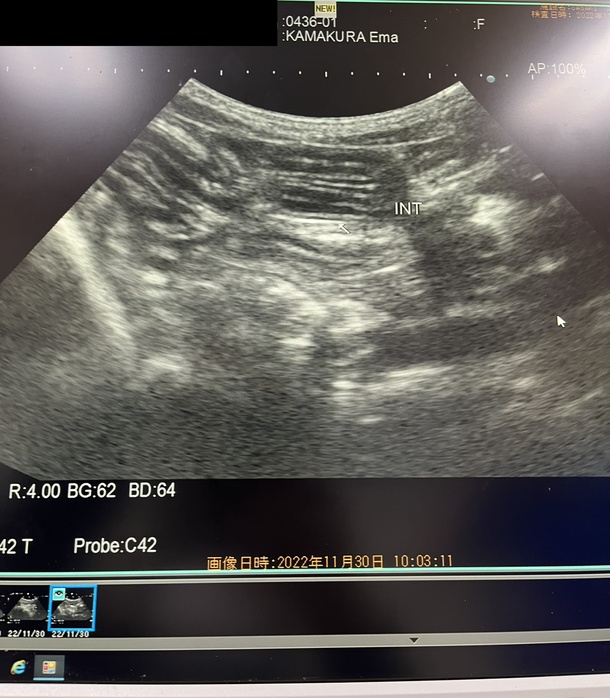

腹部エコー

腹部エコーでは腹水無しとのことで本当にホッとしました。

サービスで肝臓のエコーも撮っておいてくださり、異常なしとのことで本当に安心しました。